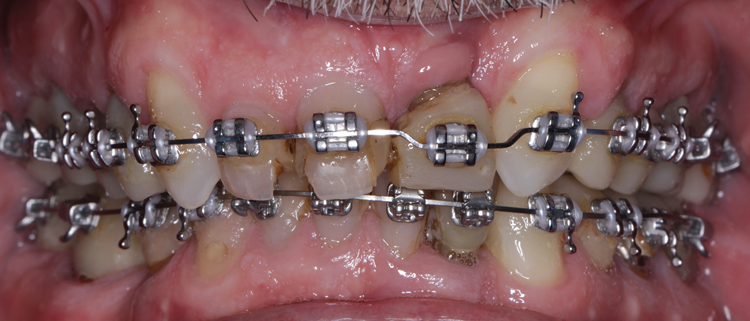

(8.) View of the maxillary and mandibular posterior full-coverage composite crowns, which were designed and milled with an increased vertical dimension position. This position was determined after intraoral testing was conducted with a leaf gauge instrument.

Figure 8

(11.) Retracted view of the patient after the initiation of orthodontic treatment. Upon completion of the orthodontic treatment, the patient will receive a full-mouth prosthetic rehabilitation with ceramic crowns. Tooth No. 9 was retained for implant site development but would eventually be extracted to place an implant-supported crown.

Figure 11